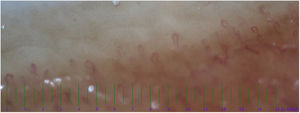

The nailfold capillaroscopy was conducted on both the KD and control groups. The abnormal capillaroscopic diameter was identified in 21 patients from KD group and four patients in the control group (Table 2). The most common abnormality in the evaluation of capillaries diameter was irregular dilatation (Fig. 1) seen in 11 (35.4%) KD patients and 4 (13.3%) in the control group. The normal capillary architecture distortions were commonly seen in KD group (n=8). On the other hand, there were no findings of architectural capillary abnormality in the control group (P=0.003). About half of KD patients had a reduction in capillary density (Fig. 2), while no similar abnormality was observed in the control group (P<0.001). There was no significant difference between KD patients and the control group in terms of morphology variations (P=0.4). Moreover, a positive correlation was observed between coronary involvement and abnormal capillaroscopic results (r=0.65, P<0.03).